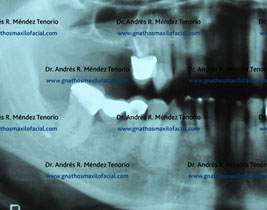

Sialolito submandibular. El paciente presenta infección y edema en piso de boca

Imágenes de la lesión, caracterizada por tejido mineralizado en el conducto de la glándula submandibular